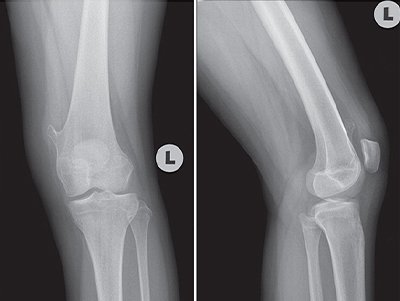

01 Nov Lump in leg By arsalan0 Comments An 11-year-old girl, a student, accompanied by her mother, came to the clinic complaining of a lump in her left leg that did not go away. She noticed the pump 15 days ago; it has not grown and is not associated with pain. She had no trauma or injury to the left leg, and the lump does not interfere with her daily activities. Her family history is unremarkable. Her physical examination revealed a lump on her left medial knee, skin over lump was normal, no ecchymosis. The lump is nontender firm, fixed bony prominence, and located on the medial distal left femur. However, there was no knee joint effusion and her knee range of motion was normal. No palpable inguinal lymphadenopathy was noticed. Plain radiography was performed and is shown below. Based on the physical examination and radiography findings, Which one of the following is the most likely diagnosis? Osteochondroma Osteoid osteoma Enchondroma Non-ossifying fibroma Fibrous dysplasia None Time's up Share article:TwitterFacebookLinkedin